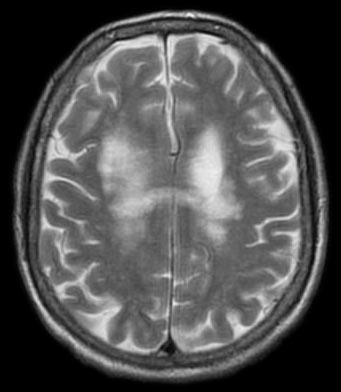

Magnetic resonance imaging (MRI) identifies plaques (areas of white matter demyelination) associated with multiple sclerosis (MS).

Gross inspection of brains with multiple sclerosis (MS) reveal white matter plaques that appear gray.

- Hemiparesis is a loss of sensation to one side (cerebral white matter, usually periventricular)